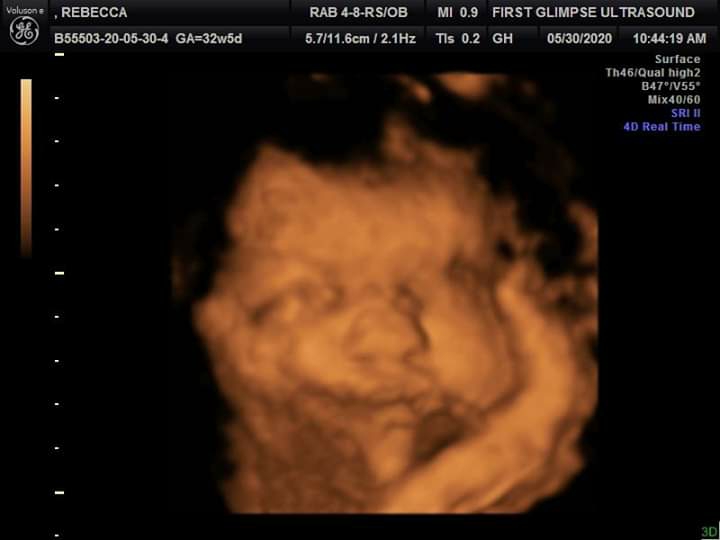

We got to see our sweet baby Star today, in 3d/4d. I'll be 32 weeks tomorrow! Shes measuring 4 pounds 5 ounces which is about a week or so ahead of schedule ( I have gestational diabetes so I knew she would be bigger but dang lol) shes got the longest legs that are measuring 2 weeks ahead of her body. Shes also got lots of hair and the cutest chunky cheeks with the sweetest smile. ❤❤ my mom got us a heart beat bear ( really it's a fox lol) and my daughter is carrying it around going this is my sister fox sister fox lol. It's been a hard pregnancy but I'm finally getting an attachment to her ( no judgements please if you want to know why I'll be happy to explain it 🤷♀️) 7 weeks till we meet her.

Yes . Shes looks just like her sister except the nose is slightly different